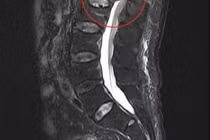

Từ khóa: Xẹp đốt sống và biến chứng